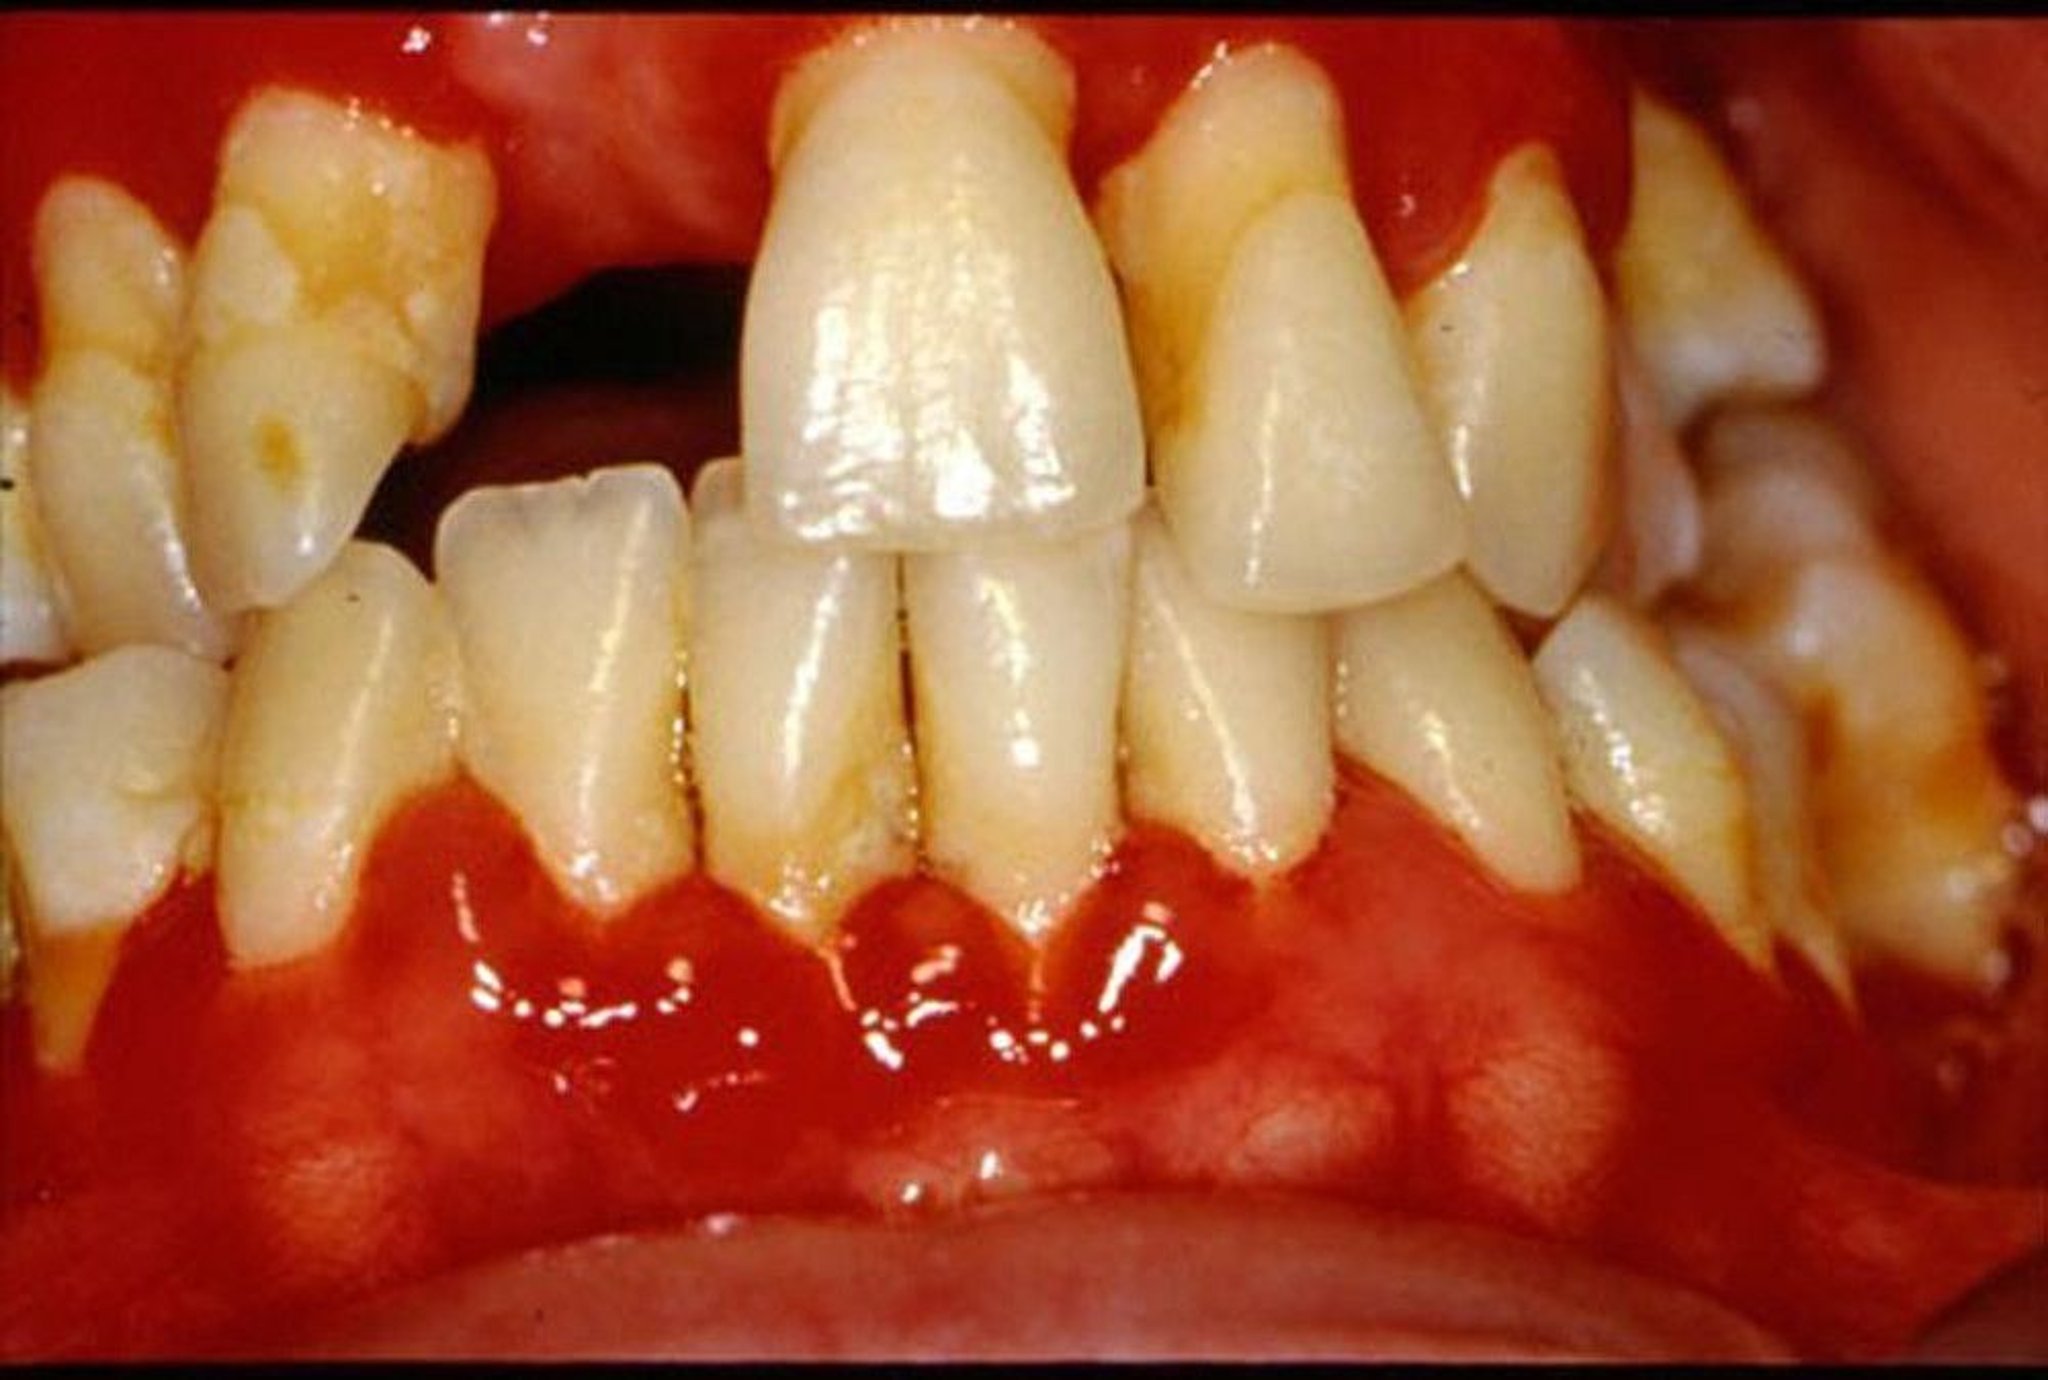

This photo shows chronic plaque-induced inflammation of the soft tissues resulting in loss of gum tissue and supporting bone, tooth movement, and loss of teeth.

Image provided by Jonathan A. Ship, DMD.